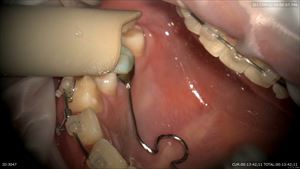

マイクロスコープ治療による精密根管治療

腐った神経が、、、、、

丁寧に汚染物を取ります。

無痛レーザー